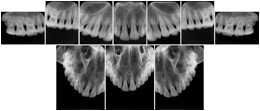

In most standard cases, images are oriented in structured layouts. These structured displays are useful to be shared between providers for reference purposes.

Table OO.1.1-1 shows structured display standard templates, where Viewset ID is based on the Japanese Society for Oral and Maxillofacial Radiology (JSOMR) classification provided by JIRA (Japan Medical Imaging and Radiological Systems Industries Association, www.jira-net.or.jp). Expected or typical teeth to be imaged location, region and designation codes are based on ISO 3950-2010, Dentistry - Designation system for teeth and areas of the oral cavity. For all the hanging protocols listed in OO.1.1-1, the value to use for Hanging Protocol Creator (0072,0008) is "JSOMR" and the value to use for Hanging Protocol Name (0072,0002) does not include "JSOMR" (e.g., "DL-S001A", not "JSOMR DL-S001A").